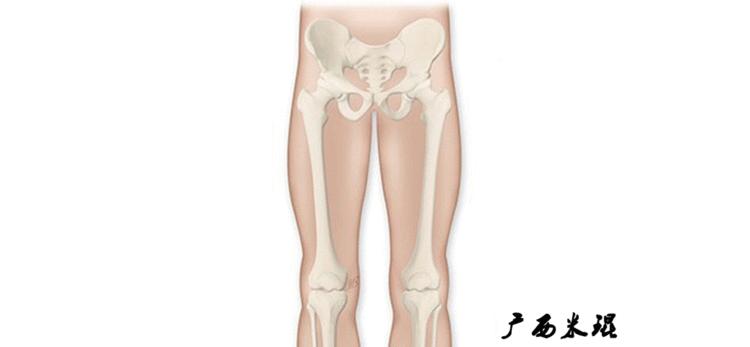

2、画出下肢的轴线

确定髋关节、膝关节、踝关节的中心点后,我们才能了解下肢的几个轴线。

(1)解剖轴

股骨和胫骨的骨干中线为解剖轴,股骨解剖轴和胫骨解剖轴的夹角正常值为174°±1°。

(2)机械轴

机械轴是连接近端和远端关节中心点的直线。

机械轴要分前后位及侧位,站立前后位(也就是冠状面)股骨头中心与踝关节中心的连线通过膝关节中心,这是下肢的机械轴线,也就是下肢力线,常说Mikulicz线。冠状面的力线评估在临床工作中最常用、最基础、最重要。